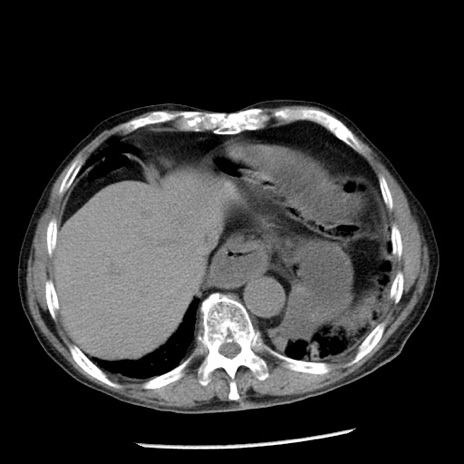

症例26(横断像)

【症例】80歳代男性

【主訴】嘔吐

【現病歴】昨晩2回嘔吐あり、今朝になっても嘔吐あり。来院。

【既往歴】胃潰瘍

【身体所見】意識清明、BT 37.6℃、BP 166/95mmHg、HR 100bpm、SpO2 97%、腹部:平坦・軟、腸蠕動音聴取良好、圧痛なし。

【データ】WBC 21900、CRP 1.46